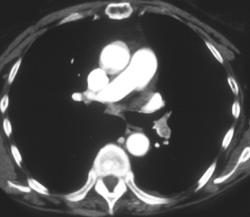

Stenosis of Both Mainstem Bronci at Anastomosis Post Transplant